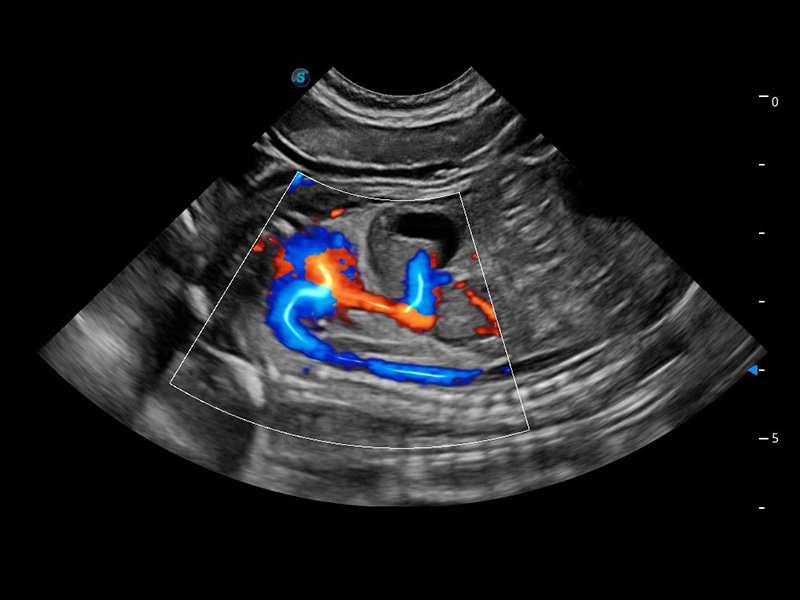

ProPet 60 作为一款高端台式动物超声设备,为动物医生的日常诊断提供了一系列贴合动物临床需求、解决临床实际问题的高级成像功能。凭借全系列高清探头,满足医生对腹部、心脏、生殖、浅表、肌骨等成像的所有需求,切实帮助您提升检查效率,提高诊断信心。

动物是人类最亲密的朋友和最值得信赖的伙伴。云顶集团官网也一直致力于探索动物专用的超声影像解决方案。 全新推出的ProPet系列,是云顶集团官网在动物超声影像智能化、专业化、精准化的一次跨越式革新。动物不能用言语来表述自己的不适,通过超声影像,ProPet系列搭建了动物医生与不同物种沟通的“桥梁”,为动物医生注入了“治愈之力”。